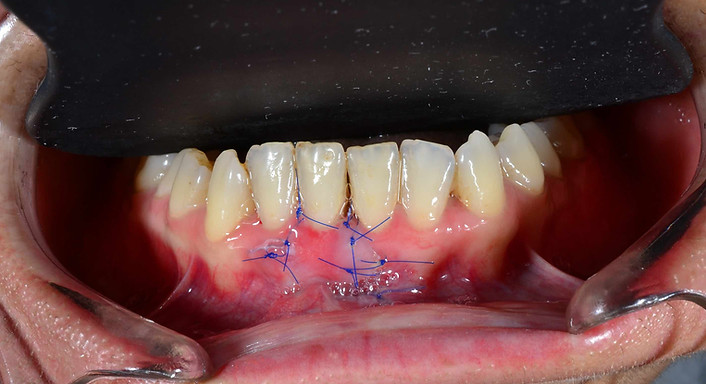

SDG Operasyonu Nasıl Yapılır?

-

Muayene ve planlama,

-

Lokal anestezi ile ağrısız işlem,

-

Damaktan ince bir doku parçasının alınması,

-

Çekilme bölgesine yerleştirilip dikişlerle sabitlenmesi,

-

1–2 haftalık iyileşme süreci,

-

Düzenli kontrol ile sonuçların değerlendirilmesi.

Operasyon yaklaşık 30–45 dakika sürer.